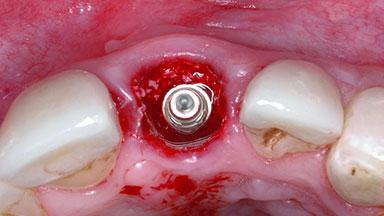

Replacement of a Failing Upper Left Central Incisor: Immediate Placement of an RC Bone Level Implant and Provisionalization

Bone Augmentation Horizontal|Simultaneous

Soft Tissue Grafting Simultaneous

Placement Protocol Immediate implant placement

Socket Integrity Damage to one or more bone walls

Bone Volume Damage to one or more socket walls